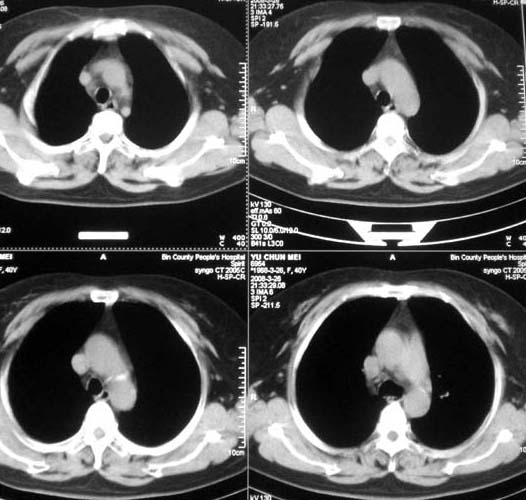

以下是引用doc张在2008-3-27 9:20:00的发言:[br]可见小叶中心型肺气肿.

以下是引用有风的日子在2008-3-27 16:59:00的发言:[br]片子上的信息与提供资料有矛盾点:到底是40岁还是56岁?[br]双下肺野可见散在、大小不等的无壁高透过影,支持小叶中心性肺气肿诊断[br]女同志有80%的症状与情绪有关,有能全靠疾病解释